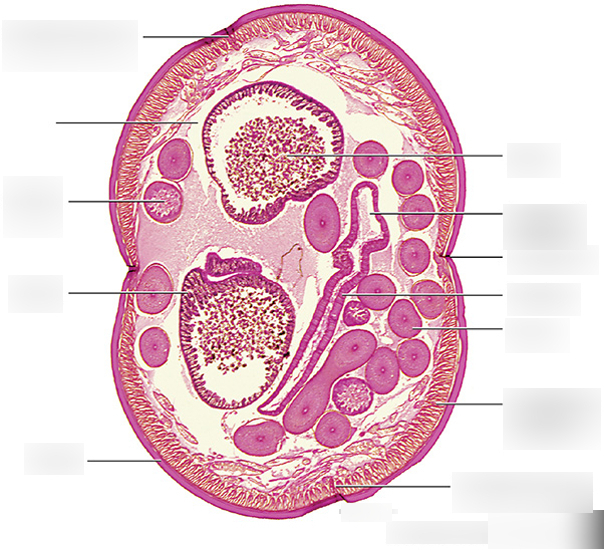

Trichinella spiralis